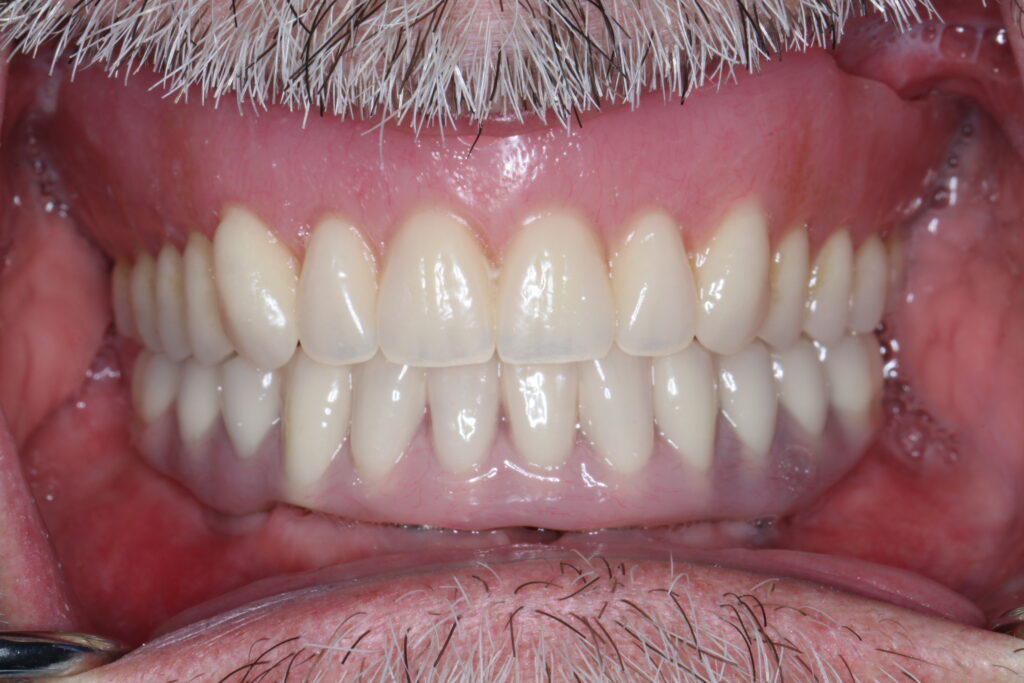

A selection of full arch fixed implant bridge patients after 5 years of wear

Oral Surgeons – Dr Han Choi, Dr Sam Goldsmith, Dr Rajiv Rajpal NSOMS

Prosthodontist – Dr Alan Payne NSOMS/Northland Prosthodontics

Dental technicians – Hosaka Takashi, DT Denture Design, Auckland, CJ Park, Project Dentistry, Auckland and Osteon Medical, Melbourne, Australia.